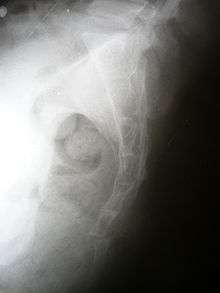

Diagnosis

X-rays are usually necessary, but this is not always the case. A physical examination will be carried out, which sometimes involves a rectal examination and/or neurologic examination.